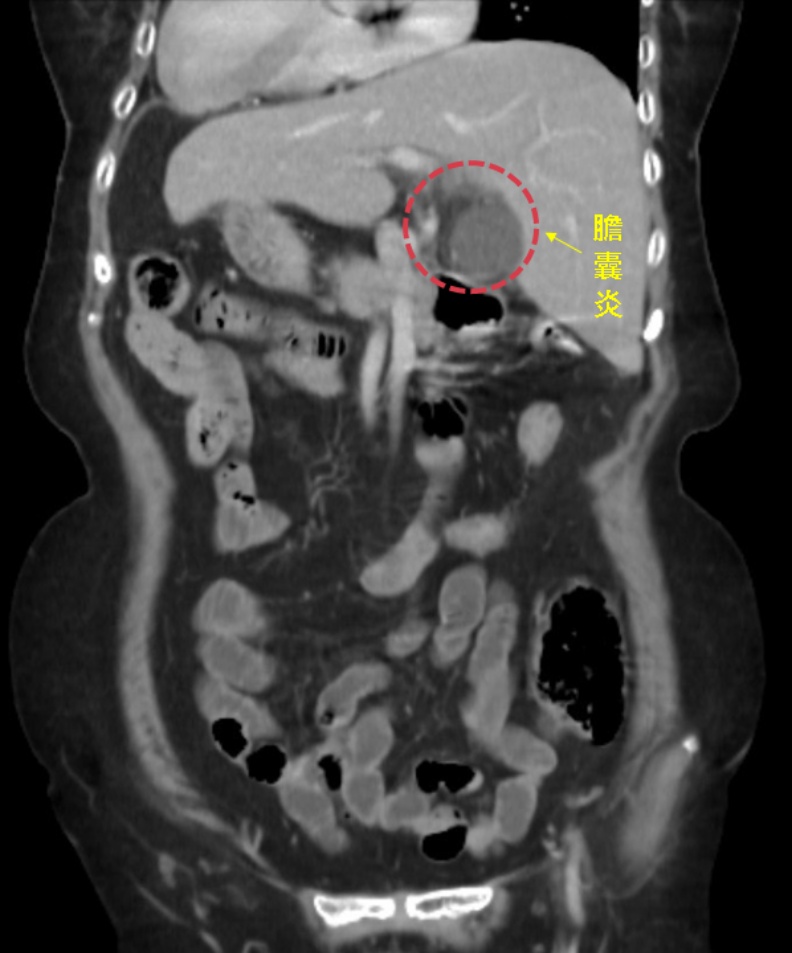

一位80歲左右的阿嬤,因左上腹痛來中國醫藥大學新竹附設醫院急診,左上腹痛一般應是胃痛或大腸發炎,做了電腦斷層發現阿嬤是一個「鏡面人」,所謂「鏡面人」就是他的內臟等器官跟一般人的位置顛倒,經過一般外科古君平醫師診斷,阿嬤是急性膽囊炎。

古君平醫師表示,所謂的「鏡面人」包括腹腔、胸腔內器官的位置與一般人剛好相反,例如一般人心臟脾臟在左邊,肝臟位於右邊,鏡面人心臟脾臟在右邊,肝臟在左邊,就好像正常人的鏡中影像,故出現「鏡面人」的稱呼。

因為鏡面人的特殊性,醫師診斷需特別小心,否則可能把病患左上腹痛當成是胃痛治療,實際上膽囊炎,發生誤診,尤其在施以手術時,與醫生的熟悉手勢有所不同而增加難度。膽囊切除是一個很常見的手術,膽囊功能儲存膽汁,膽汁是肝臟製造,所以膽囊切除之後,肝臟還是會正常分泌製造膽汁,因此,阿嬤切除膽囊,對她的生活並不會有太大影響。大部分的人可能在術後一個月左右會有容易拉肚子的情形,不過,等肝臟適應這種情況後,就可以恢復正常生活。